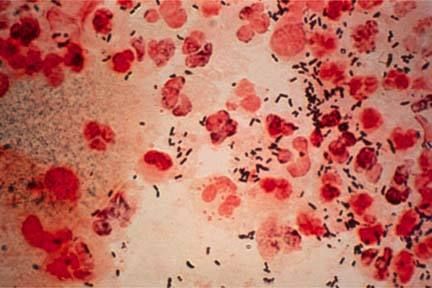

淋病是淋病奈瑟菌引起的以泌尿生殖系统化脓性感染为主要表现的性传播疾病。淋菌为革兰氏阴性双球菌,呈肾形,成双排列,离开人体不易生存,一般消毒剂容易将其杀灭。多发生于青年男女。大多数是由性接触进行传播。那么产生淋病会出现什么症状,下面我们请北京京城皮肤医院的专家给大家讲解一下。